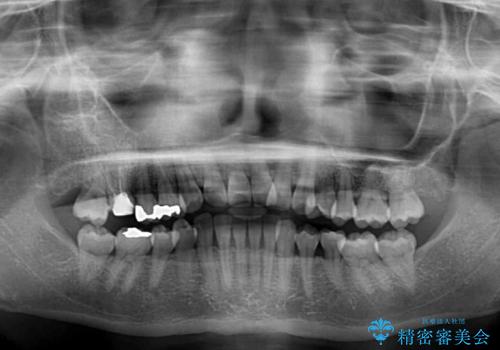

- むし歯治療を契機に、長年気にしていた前歯のクロスバイトの改善を希望された患者様です。

汚れが溜まりやすく、歯ぎしりがうまくできないため、インビザラインを用いて矯正治療を行うこととしました。

インビザラインによる前歯のクロスバイトの改善は、治療期間中に前歯でしか咬めない時期が続いたり、歯肉退縮や歯髄壊死のリスクが高まったりと、治療中にトラブルを抱えることがあります。

特に上顎側切歯(真ん中から2番目の歯)が舌側に引っ込んでいるケースは、インビザラインでは改善しきれないことがあると言われています。